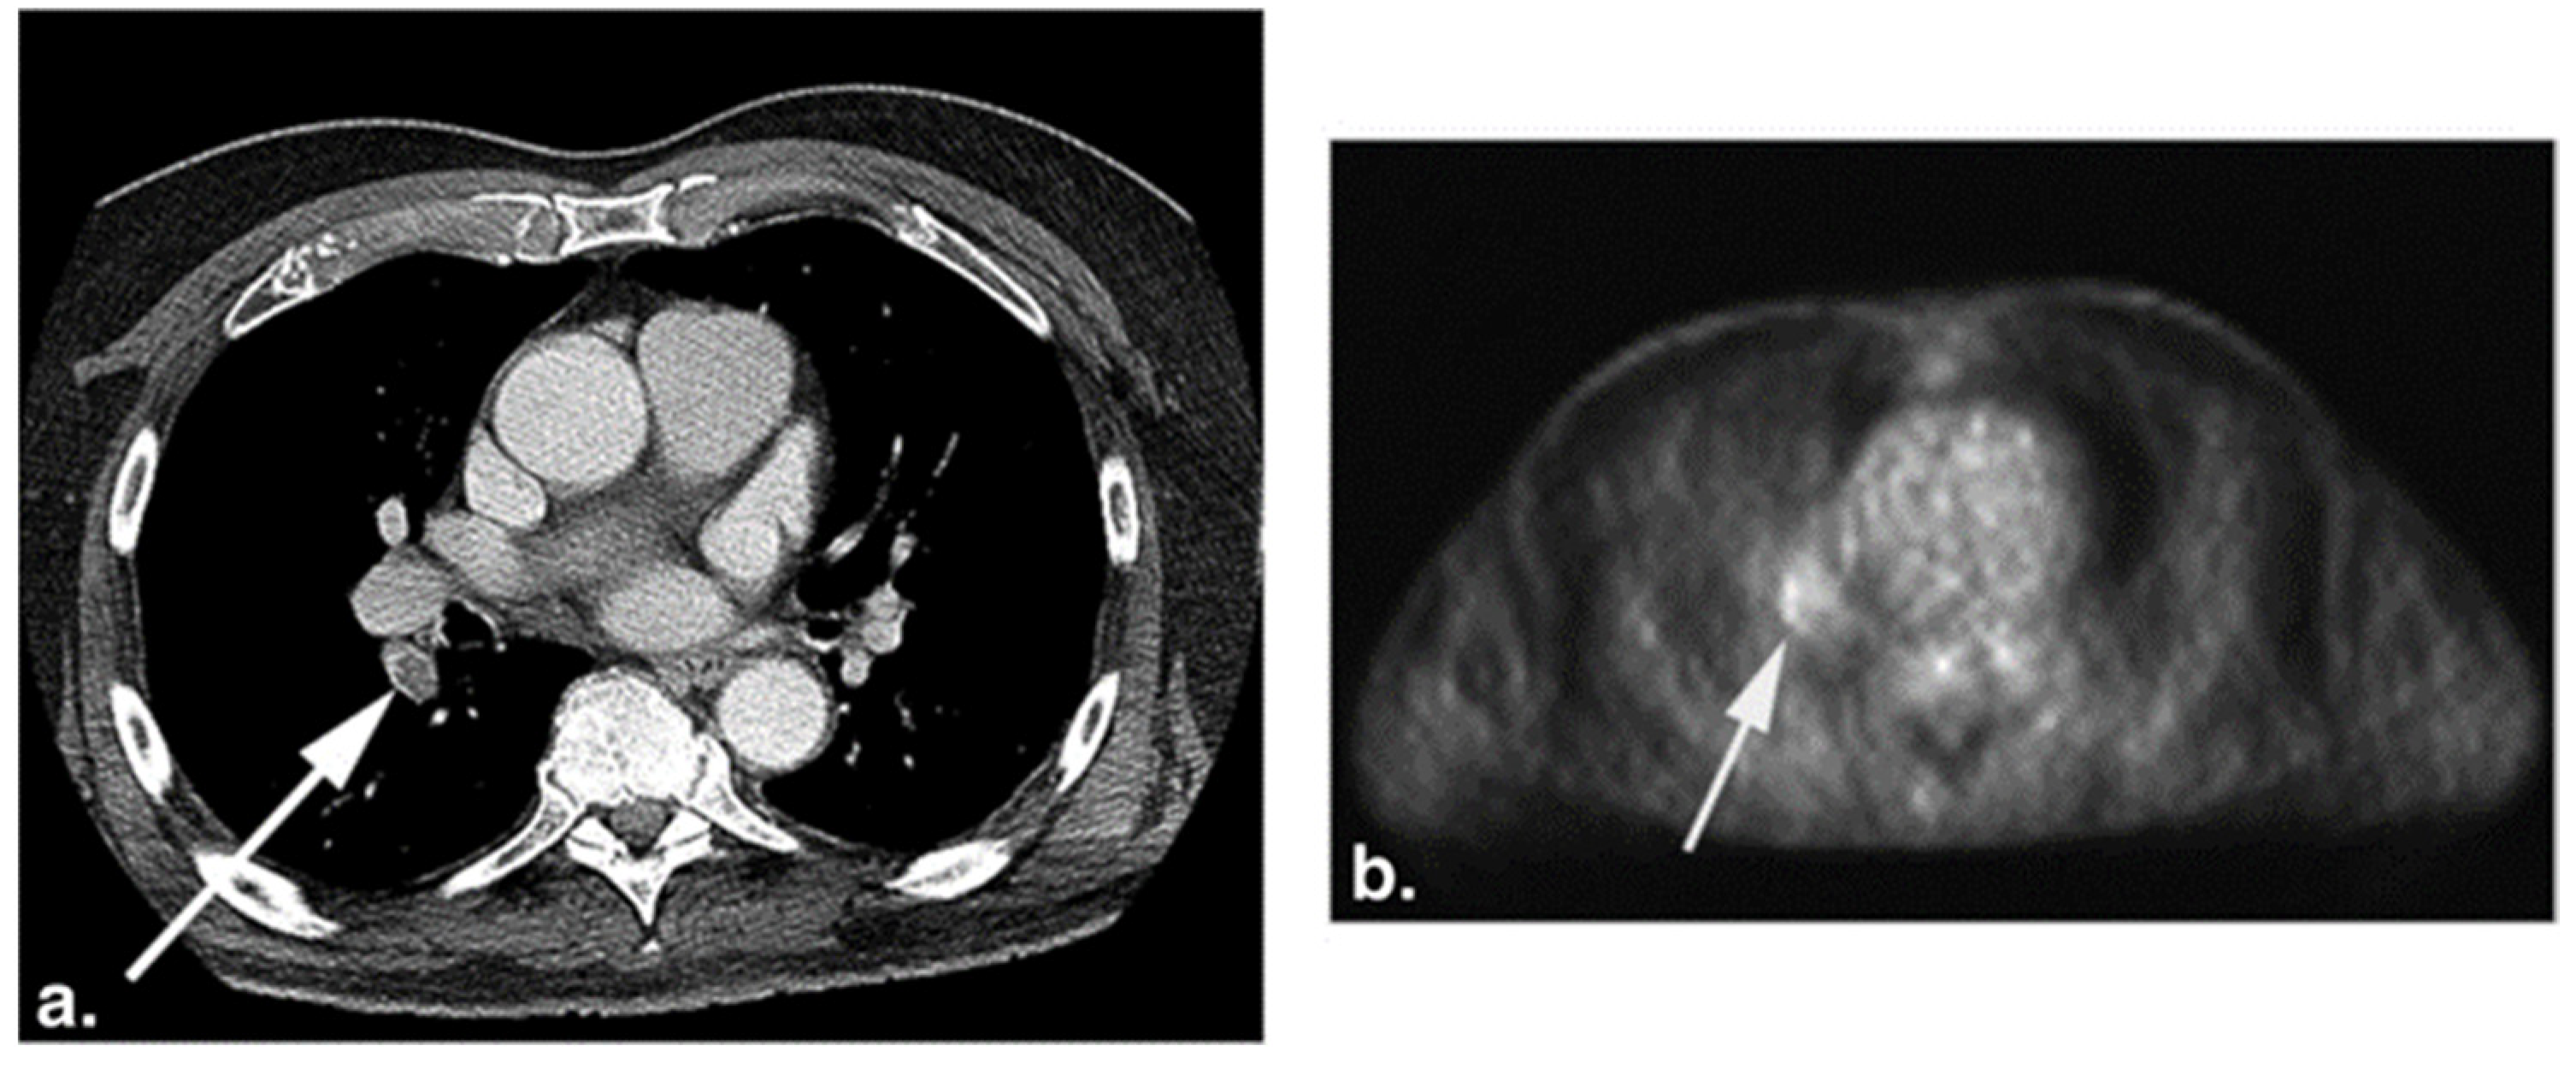

Evidence points toward NaF uptake as a significant clinical metric for atherosclerosis (Figure 2). Kwiecinski at al. and Kitagawa et al. both found that focal coronary NaF uptake on the index scans significantly correlates with the incidence of myocardial infarction [47,48]. As such, findings on NaF-PET/CT may therefore serve as a tool to assess the future risk of atherosclerosis complications. Other studies by Rojulpote et al. and Patil et al. have correlated the NaF uptake of vital and laboratory values such as blood pressure and the triglycerides-to-high-density lipoprotein ratio, respectively [49,50]. In addition, NaF uptake has been associated with widely used clinical scores for cardiovascular disease burden, including the Framingham Risk Score, atherosclerotic cardiovascular disease (ASCVD) risk scores calculated by the Pooled Cohort Equation, and CHADS2/CHADS2-VASc [34,51,52,53,54].

Figure 2.

CT, NaF-PET, and fused NaF-PET/CT images of clinically normal (a) 25- and (b) 61-year -old subjects’ hearts. Green line delineates the region of interest around the heart analyzed to calculate the global cardiac calcification scores, which are 12,492.44 (a) and 18,424.70 (b). Despite the relatively increased NaF uptake in the PET scan of the subject’s heart (b), there is no visible calcification in the corresponding CT scan. The disparity between two modalities alludes to CT-visible macrocalcification as end-stage disease process, while NaF uptake may reflect early pathological, molecular changes (from Raynor et al. [94] with permission).